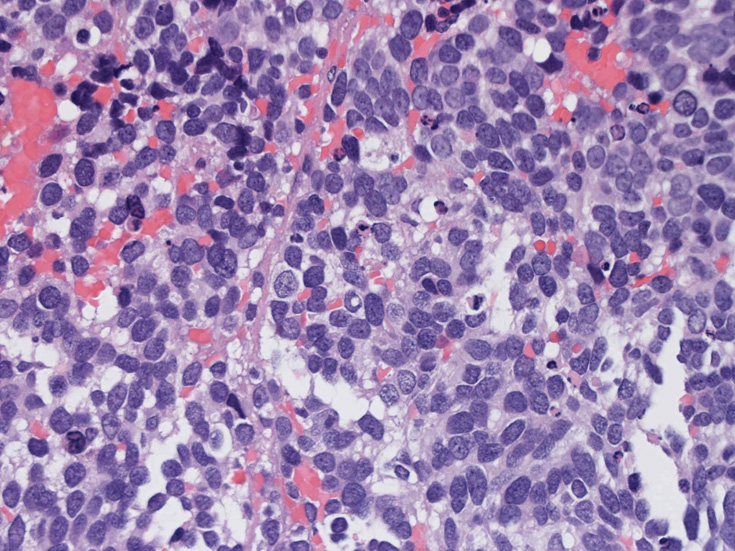

30歳代男性 鼻腔腫瘤の生検組織

厳密にはalveolar patternが明らかではなく, solid typeに入る症例かもしれない。異型細胞増殖胞巣が線維化組織に取り囲まれるように散在している. 小さな生検組織のため全体像が不明である。

鼻腔腫瘤生検組織